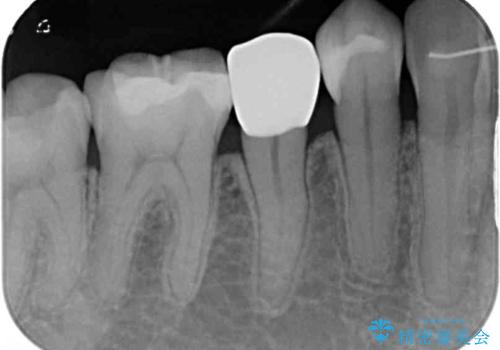

オールセラミッククラウンにて補綴することとしました。

しみる症状はなくなり、見た目もきれいになり、とても満足されました。